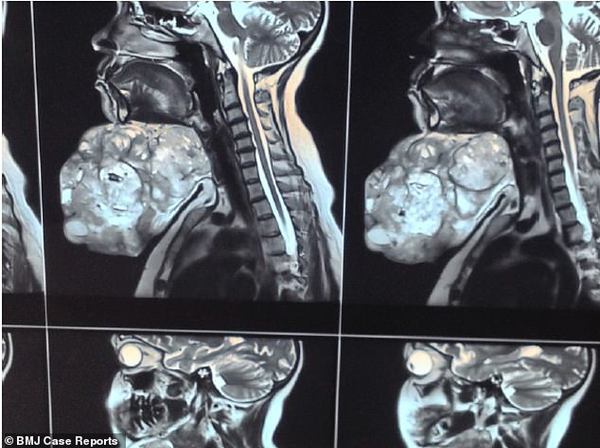

【环球网综合报道】据英国《每日邮报》12月7日报道,18年间,印度一位47岁妇女在下巴处长了一颗近9斤重的肿瘤,现已通过手术切除。

术前术后对比图展示了,外科医生为一名妇女切除下巴的巨大肿瘤后,该妇女发生的巨大变化。这位47岁的妇女告诉医生,这颗奇怪的肿瘤长了近20年。

印度北方邦的医生表示,一般新生儿的体重只有6斤左右,近9斤重的肿瘤着实让人吃惊。他们对这个病例十分感兴趣,于是决定将其发表在著名刊物《英国医学病理报告杂志》上。阿拉哈巴德Moti Lal Nehru医学院的研究小组称,这种大型多形性腺瘤在医学文献中十分罕见。这位妇女的病例报告中,外科主治医生Ashutosh Rai写道:“即使是在现代生活中,出现如此大型的肿瘤还是十分令人吃惊的?!?/p>

他们透露,因为这位妇女害怕进行激烈的手术,所以她逃避了18年才来就医。最后,这位妇女决定在家乡阿拉哈巴德的医院进行治疗。她表示,这些年来这颗肿瘤一直缓慢生长,但过去的这两年间却突然急速增长。

虽然肿瘤目前已经切除,但仍不知道渗出的液体是否会产生气味,也不知道颜色为何。外科医生没有透露任何手术细节,但他们表示,术后5个月内病人恢复良好,没有任何并发症发生。

多形性腺瘤又称混合瘤,是生长在涎腺的良性肿瘤。数据显示,这是最常见的涎腺肿瘤,占所有涎腺肿瘤的70%。但目前尚不清楚良性涎腺肿瘤的发病原因。(实习编译:张蓝艳 审稿:李宗泽)